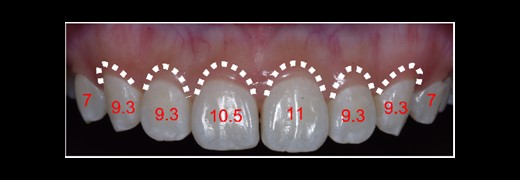

The length of the tooth crowns was clinically measured on the dental model (see Fig. 2), whereas the anatomical length was evaluated through CBCT images (see Figs 3 and 4). Based on the anatomical crown length, a smile design was created, and the patient was presented with a simulated smile before treatment (Figs 5 and 6). Upon approval of the simulated smile, a treatment plan was devised, establishing the future bone margin at 3-mm apical to the cementoenamel junction (CEJ) for each tooth, as indicated in Fig. 7.

In CBCT, determine the CEJ of each tooth to ascertain the anatomical crown length.

DSD with the anticipated gingival margin determined by the CEJ location.

Simulating the position of the proposed bone margin 3 mm apical to the anticipated gingival margin.